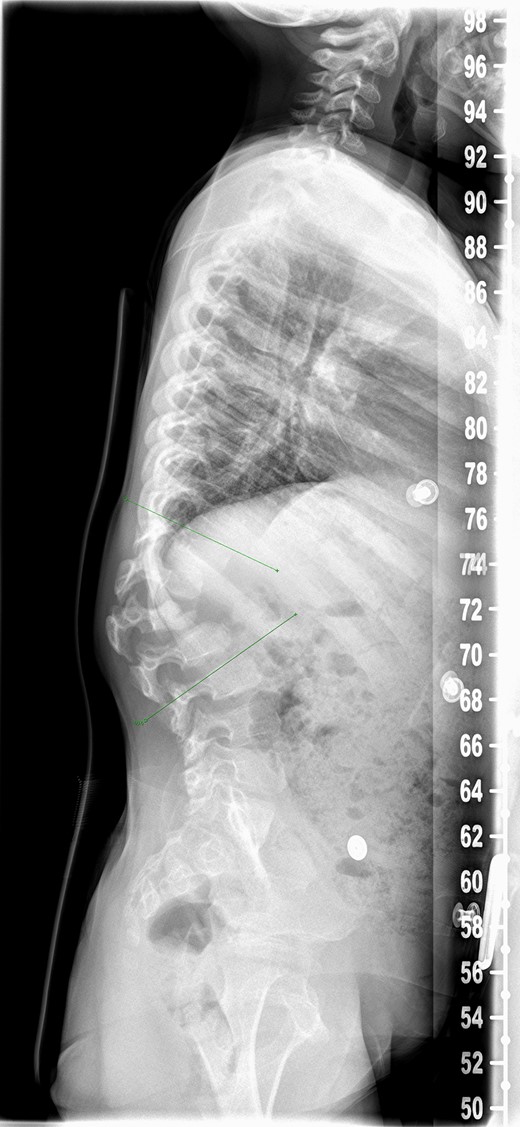

Patient was reviewed 1 month after the surgery and radiographs (Fig. 3a and b) revealed heterotopic ossification in the paraspinal soft tissue. Matured mineralized bone was clearly seen near the distal end of the spinal construct. Wound was healed and there was no further discharge. No further intervention has been planned as patient remains asymptomatic with good radiographic correction of kyphosis.

One month postoperative spine radiograph in (a) lateral view and (b) anteroposterior view showing heterotopic ossification.